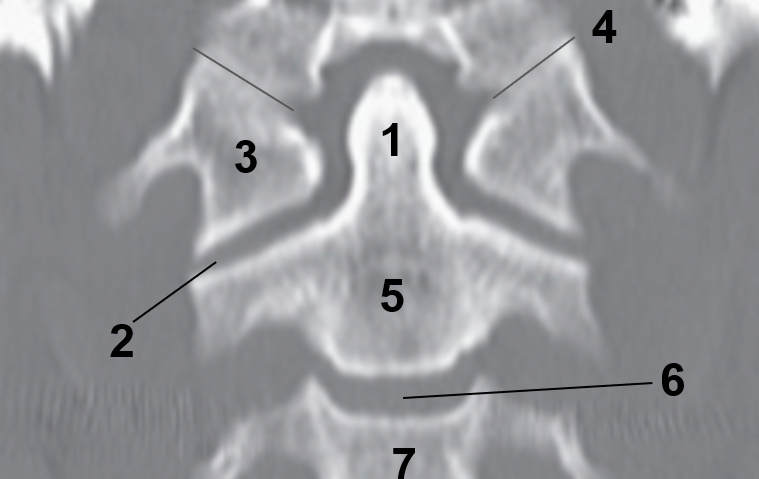

1?

Nasal Bone

2?

Maxillary Sinus

3?

External Acoustic Meatus

4?

Pons

5?

Cerebellum

6?

Mastoid Air Cells

7?

Mandibular Condyles

8?

Sphenoid Bone

9?

Maxillary Bone